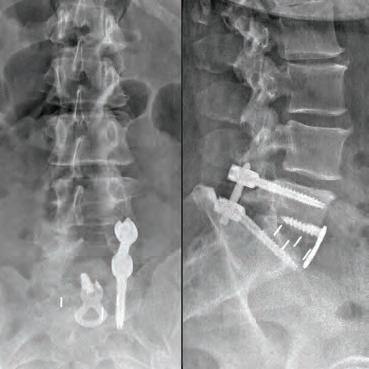

SURGERY: L5/S1 360° LUMBAR FUSION

Stephen P. Courtney, MD

Fellowship-Trained Orthopedic Spine Surgeon

Over 26 Years of Experience

Dr. Courtney is a board-certified orthopedic spine surgeon located in Plano, Texas. A Louisiana native, he attended Louisiana State University for medical school, and completed residency at Texas A&M followed by a fellowship at the Florida Neck and Back Institute.

SPECIALTIES:

• Back Pain

• Neck Pain

• Spine Pain

• Disc Replacement

• Microdiscectomy

• Spinal Fusion

• Minimally Invasive Surgery

• Steroid Injections

• Physical Therapy